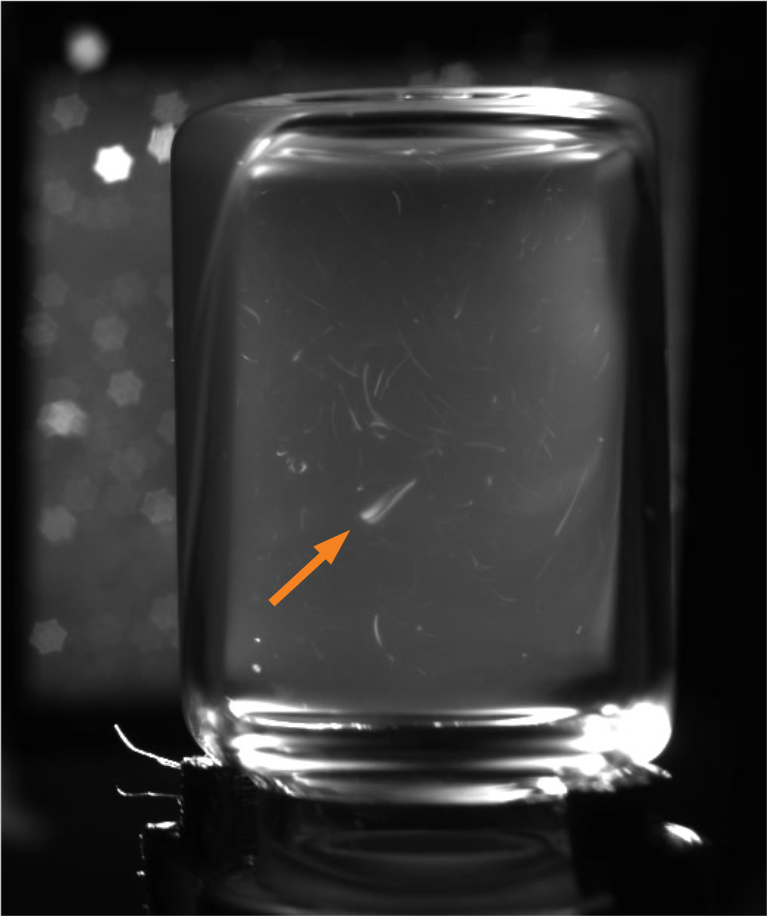

Correct lighting conditions are a prerequisite for identifying anomalies within liquid vaccines, since, due to a lack of contrast, their identification under natural lighting conditions is currently infeasible for human or automated visual inspection. A light intensity must be found that is sufficient for illuminating the vial while providing a moving contrast to identify the smallest particles [20]. To obtain a moving contrast human inspectors shake the vials to induce a swirl during manual inspections. Automated approaches meanwhile, such as the semi-automatic Seidenader V90+ inspection machine, use servo motors to stir up particles inside the vials. However, this approach has a side-effect of creating bubbles within the liquid. Furthermore, light reflections and dust particles resting on the outer surface of the vials can often be mistaken for anomalies within the liquid [20]. Opaque suspensions further increase the task difficulty by obscuring anomalies, which as a result are frequently only briefly visible. Figure 1 depicts some of these challenges.

Motion Blur: One of the challenges regarding tuning the camera prior to recording the vials, was to find a depth of field that provides a sharp focus for all the particles within the suspensions. This means that the aperture size has to be narrowed to enable a sufficiently deep depth of field. A smaller aperture requires longer shutter speeds in order for sufficient light to reach the camera’s sensor. Despite increasing the light emitted by our strobe to the maximum setting, we are only able to record using 25 fps, and as a result the initial 20 – 40 frames from each recording suffer from motion blur (Examples are provided in Figure 3). Therefore, due to particles’ increased velocity after the vial is rotated using the motor, even good particles appear elongated during the initial frames of each recording.